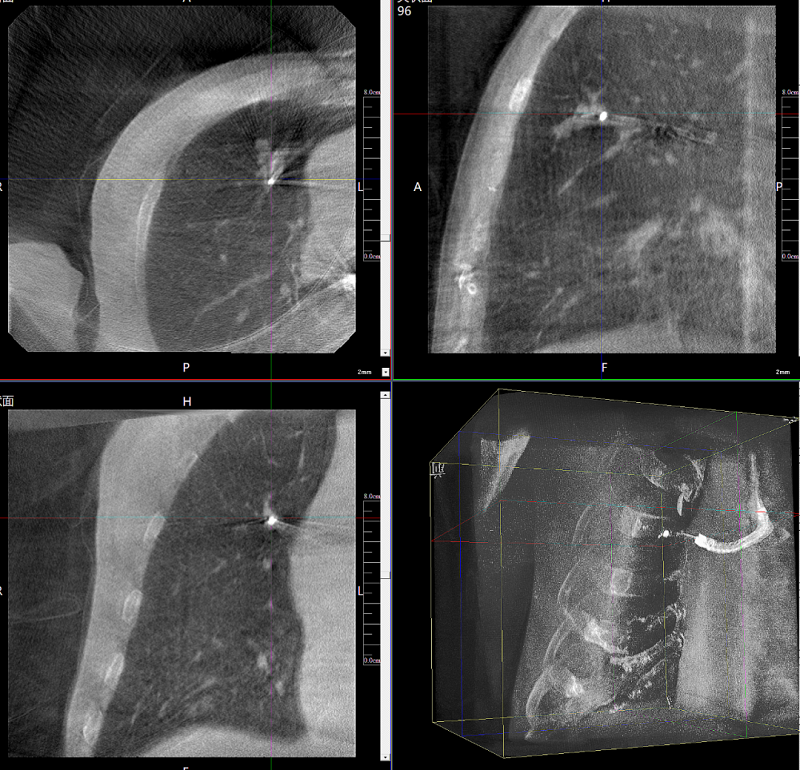

病例3:超声支气管镜下肺活检(80岁)

三维C形臂还可以创新性地应用在呼吸介入领域。例如,在经皮穿刺或经支气管镜肺结节活检、定位、消融等场景中,用于确认工具是否到达病灶、消融范围是否完全覆盖病灶等。

二维影像无法准确判断工具是否到达病灶

三维各切面影像都显示工具达到病灶内